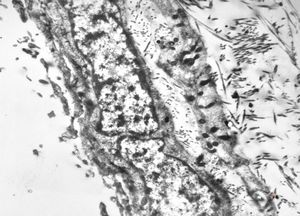

rabbit spinal cord trauma